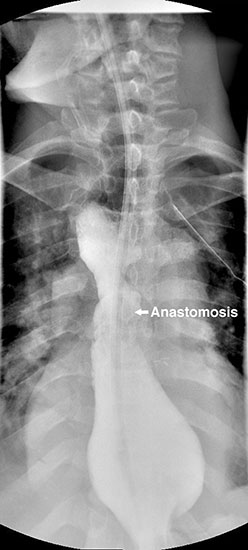

The gastric conduit was advanced into the thoracic cavity and rotated in an organo-axial fashion, such that the fundus was the most cephalad portion of the gastric conduit. With this rotation, the conduit had adequate length to reach the proximal esophagus and was not under tension. A hand-sewn, single-layered anastomosis was then performed between the esophagus and the gastric conduit (Figure 3).

Figure 4. Postoperative barium swallow demonstrating free flow through the anastomosis with no residual stricture.

The patient had an uncomplicated course. His nasogastric tube was removed on postoperative day five. A water-soluble esophageal swallow study on postoperative day six demonstrated normal flow of contrast through the anastomosis and stomach into the jejunum, with no evidence of leak or obstruction (Figure 4). The patient was discharged to home on regular diet on postoperative day eleven. Pathologic analysis of the specimen revealed multiple strictures within the esophagus, to a diameter as narrow as 5 mm, and no evidence of malignancy. The patient had complete resolution of his dysphagia on 9 month follow-up and was returning to his baseline weight.